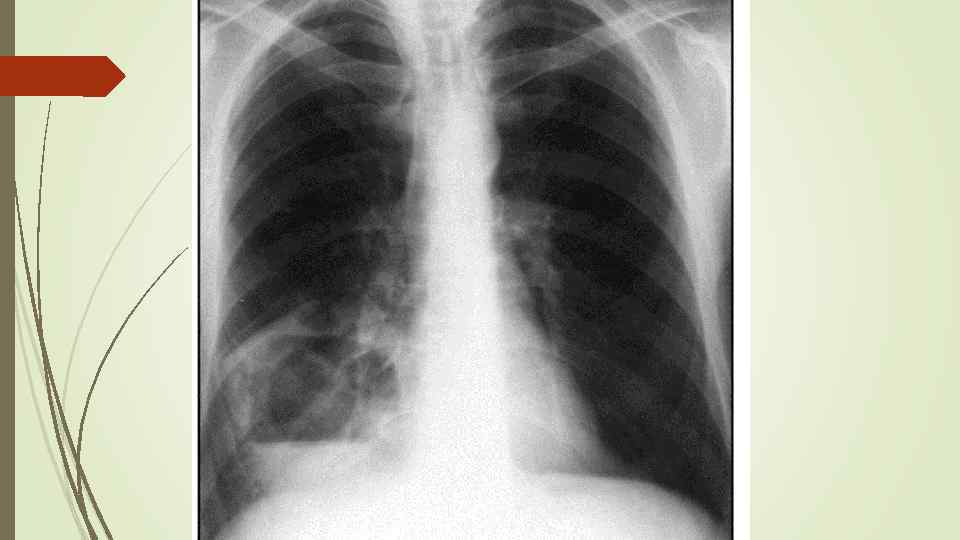

1 week later

1 week later

leaving behind only an area of rarefied lung parenchyma.

leaving behind only an area of rarefied lung parenchyma.